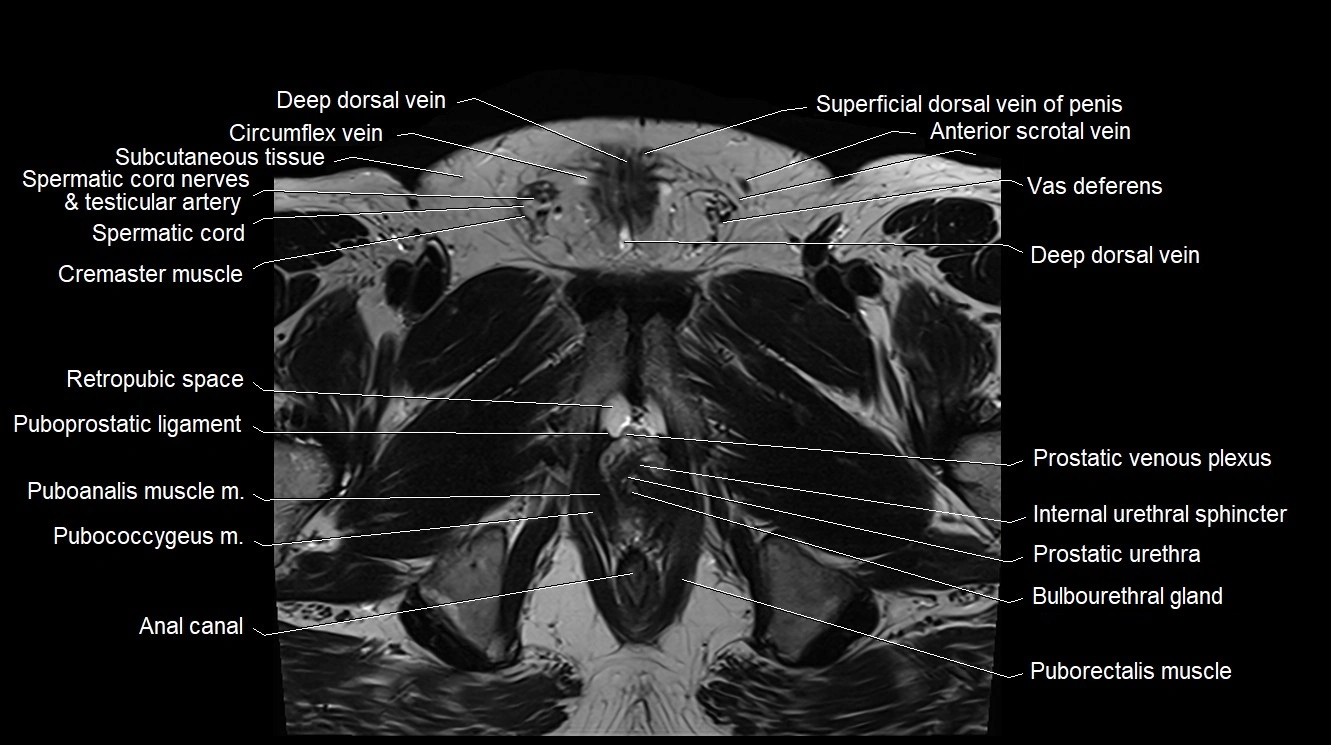

MRI image